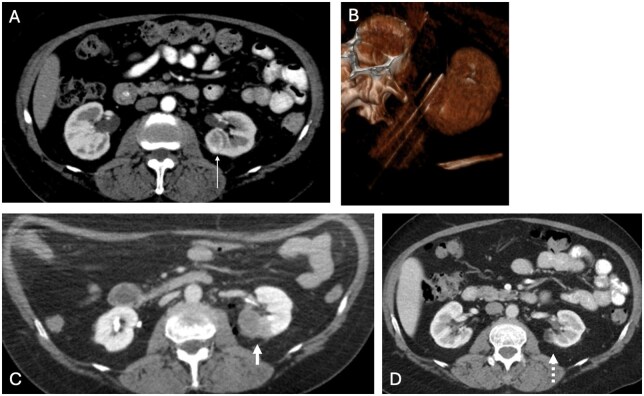

影像引导下的微创肿瘤消融技术是治疗各种不可切除软组织肿瘤的安全、有效的方法。标准的热消融方法包括射频消融、微波消融和冷冻消融。然而,新的非热和/或非侵入性消融技术现在可作为治疗软组织肿瘤的替代选择,特别是那些靠近关键结构或易受热能吸收效应影响的软组织肿瘤。本文讨论了四种新兴的消融技术:不可逆电穿孔、脉冲电场、高强度聚焦超声和组织切片法。虽然评估这些消融技术的安全性和有效性的临床试验还处于早期阶段,但初步结果在治疗不同阶段的各种癌症方面是有希望的。这些包括与化疗和免疫治疗联合使用时的潜在协同效应。

Minimally invasive image-guided tumor ablation techniques have been established as safe, effective methods to treat a variety of unresectable soft tissue tumors. Standard thermal ablation methods include radiofrequency ablation, microwave ablation, and cryoablation. However, newer non-thermal and/or non-invasive ablation techniques are now available as alternative options to treat soft tissue tumors, particularly those that are near critical structures or otherwise susceptible to thermal energy sink effects. The 4 types of emerging ablation techniques discussed in this review are as follows: irreversible electroporation, pulsed electric field, high-intensity focused ultrasound, and histotripsy. While the clinical trials evaluating the safety and efficacy of these ablation techniques are in their early stages, initial results are promising in the treatment of various cancers at different stages. These include potential synergistic effects when combined with chemotherapy and immunotherapy.